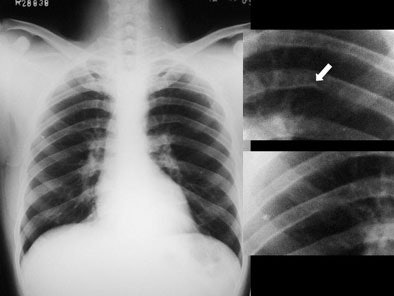

Systemic examination revealed evidence of a grade 2/6 ejection systolic murmur at the aortic area. Resting echocardiogram (ECG) revealed left ventricular hypertrophy and left atrial enlargement. Two-dimensional echo showed tricuspid aortic valve with no valvular regurgitation and coarctation of the aorta. The chest roentgenogram revealed a focal convexity to the descending aorta just distal to the aortic arch. Rib notching was present at both sides. [Figure 1]

| Figure 1. |